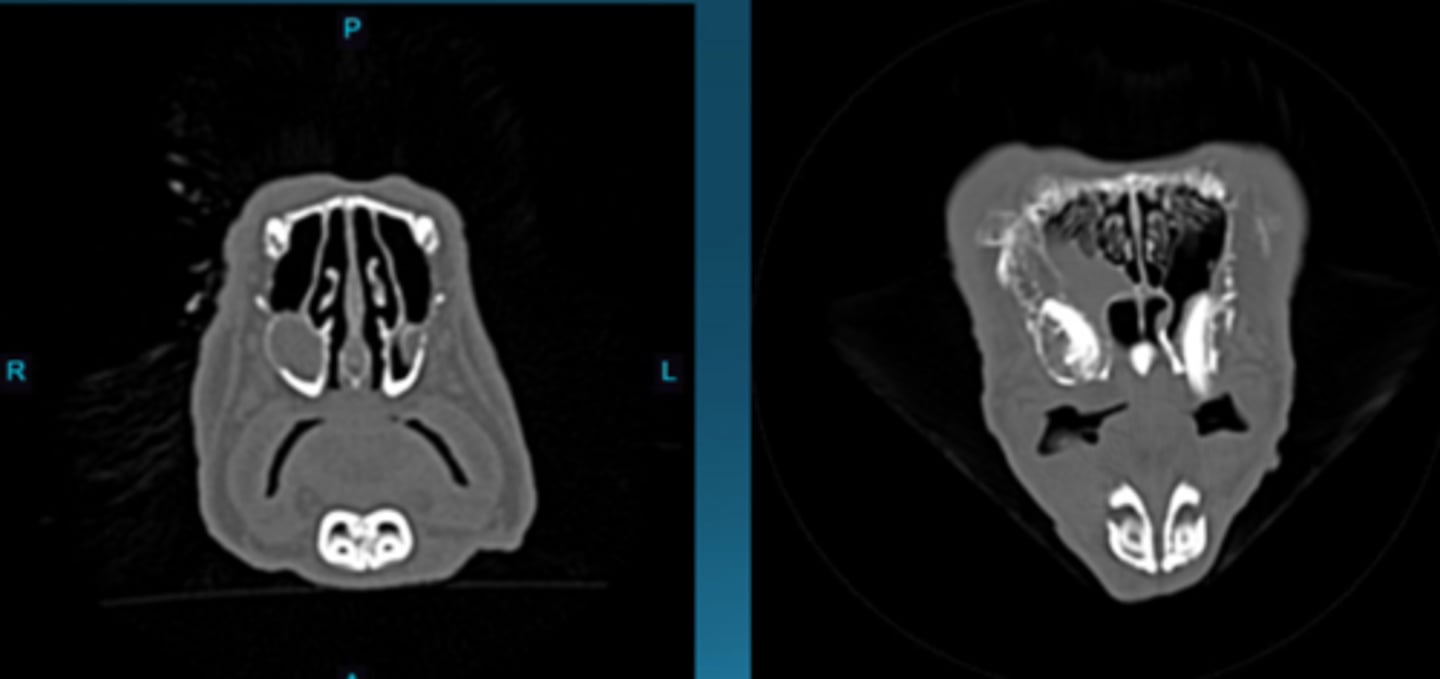

CT

What type of imaging is this in rabbits to see dental disease?

Unilateral exophthalmia from a retrobulbar mass typically an ABSCESS associated with odontogenic infection

What is happening in this rabbit?

Streptococcus and Fusobacterium

TREATMENT = antibiotics or euthanasia

Unilateral exophthalmia in rabbits is typically associated with odontogenic infection. What are the most common bacteria isolated from these abscesses? What are the typical treatments?